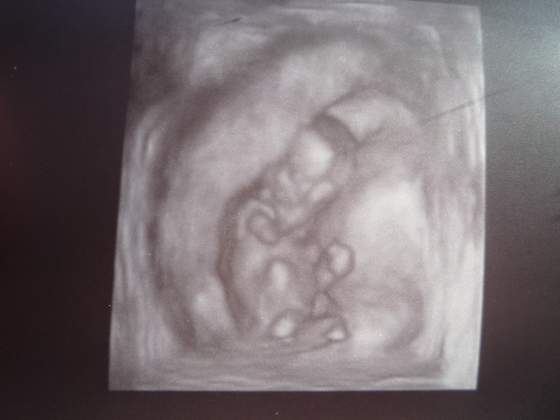

jejc.. jakie cudowne te zdjęcia

Dziś byłam w Kościele z M i byliśmy u spowiedzi i jak usiadłam już po w ławce to też poczułam takie lekkie zadrżenie jakby jakaś galareta

nie wiem jak to inaczej opisac, i zazwyczaj sa jak leze z kompem na lozku jakos dziwnie wygieta. Najpierw nie chcialo mi sie wierzyc bo dosc wczesnie, ale za 3 razem juz bylam pewna. Po jedzeniu dzidzia ma troche mniej miejsca bo zoladek tez sie rozpycha.